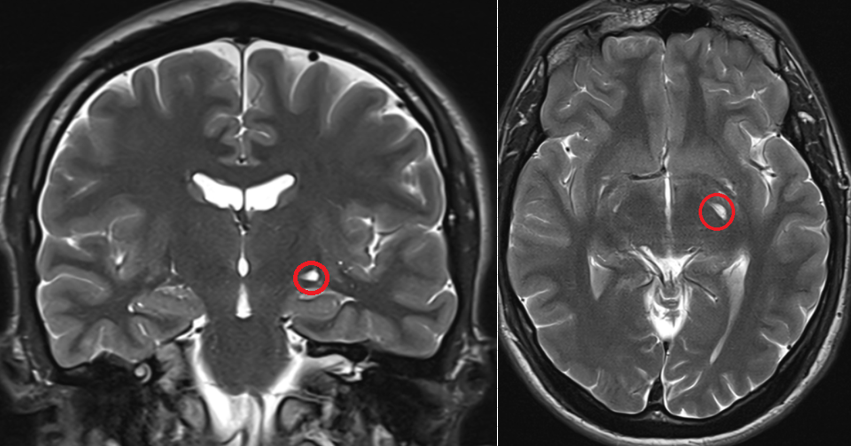

Czy jest ktoś w stanie mi wytlumaczyc dlaczego nagle mogla mi sie zacząć trzęść szyja i kark? Za każdym razem jak napne kark przykładowo przy ruszaniu głową albo gdy np. robie planka albo probuje sie na drążku podciągnąć, czy zwyczajnie zmienić pozycje na krześle to czuje jak mi zaczyna drżeć cały kark jak galareta i za tym idzie głowa. Nigdy wcześniej tak nie miałem, a trwa to już z 2 miesiące i